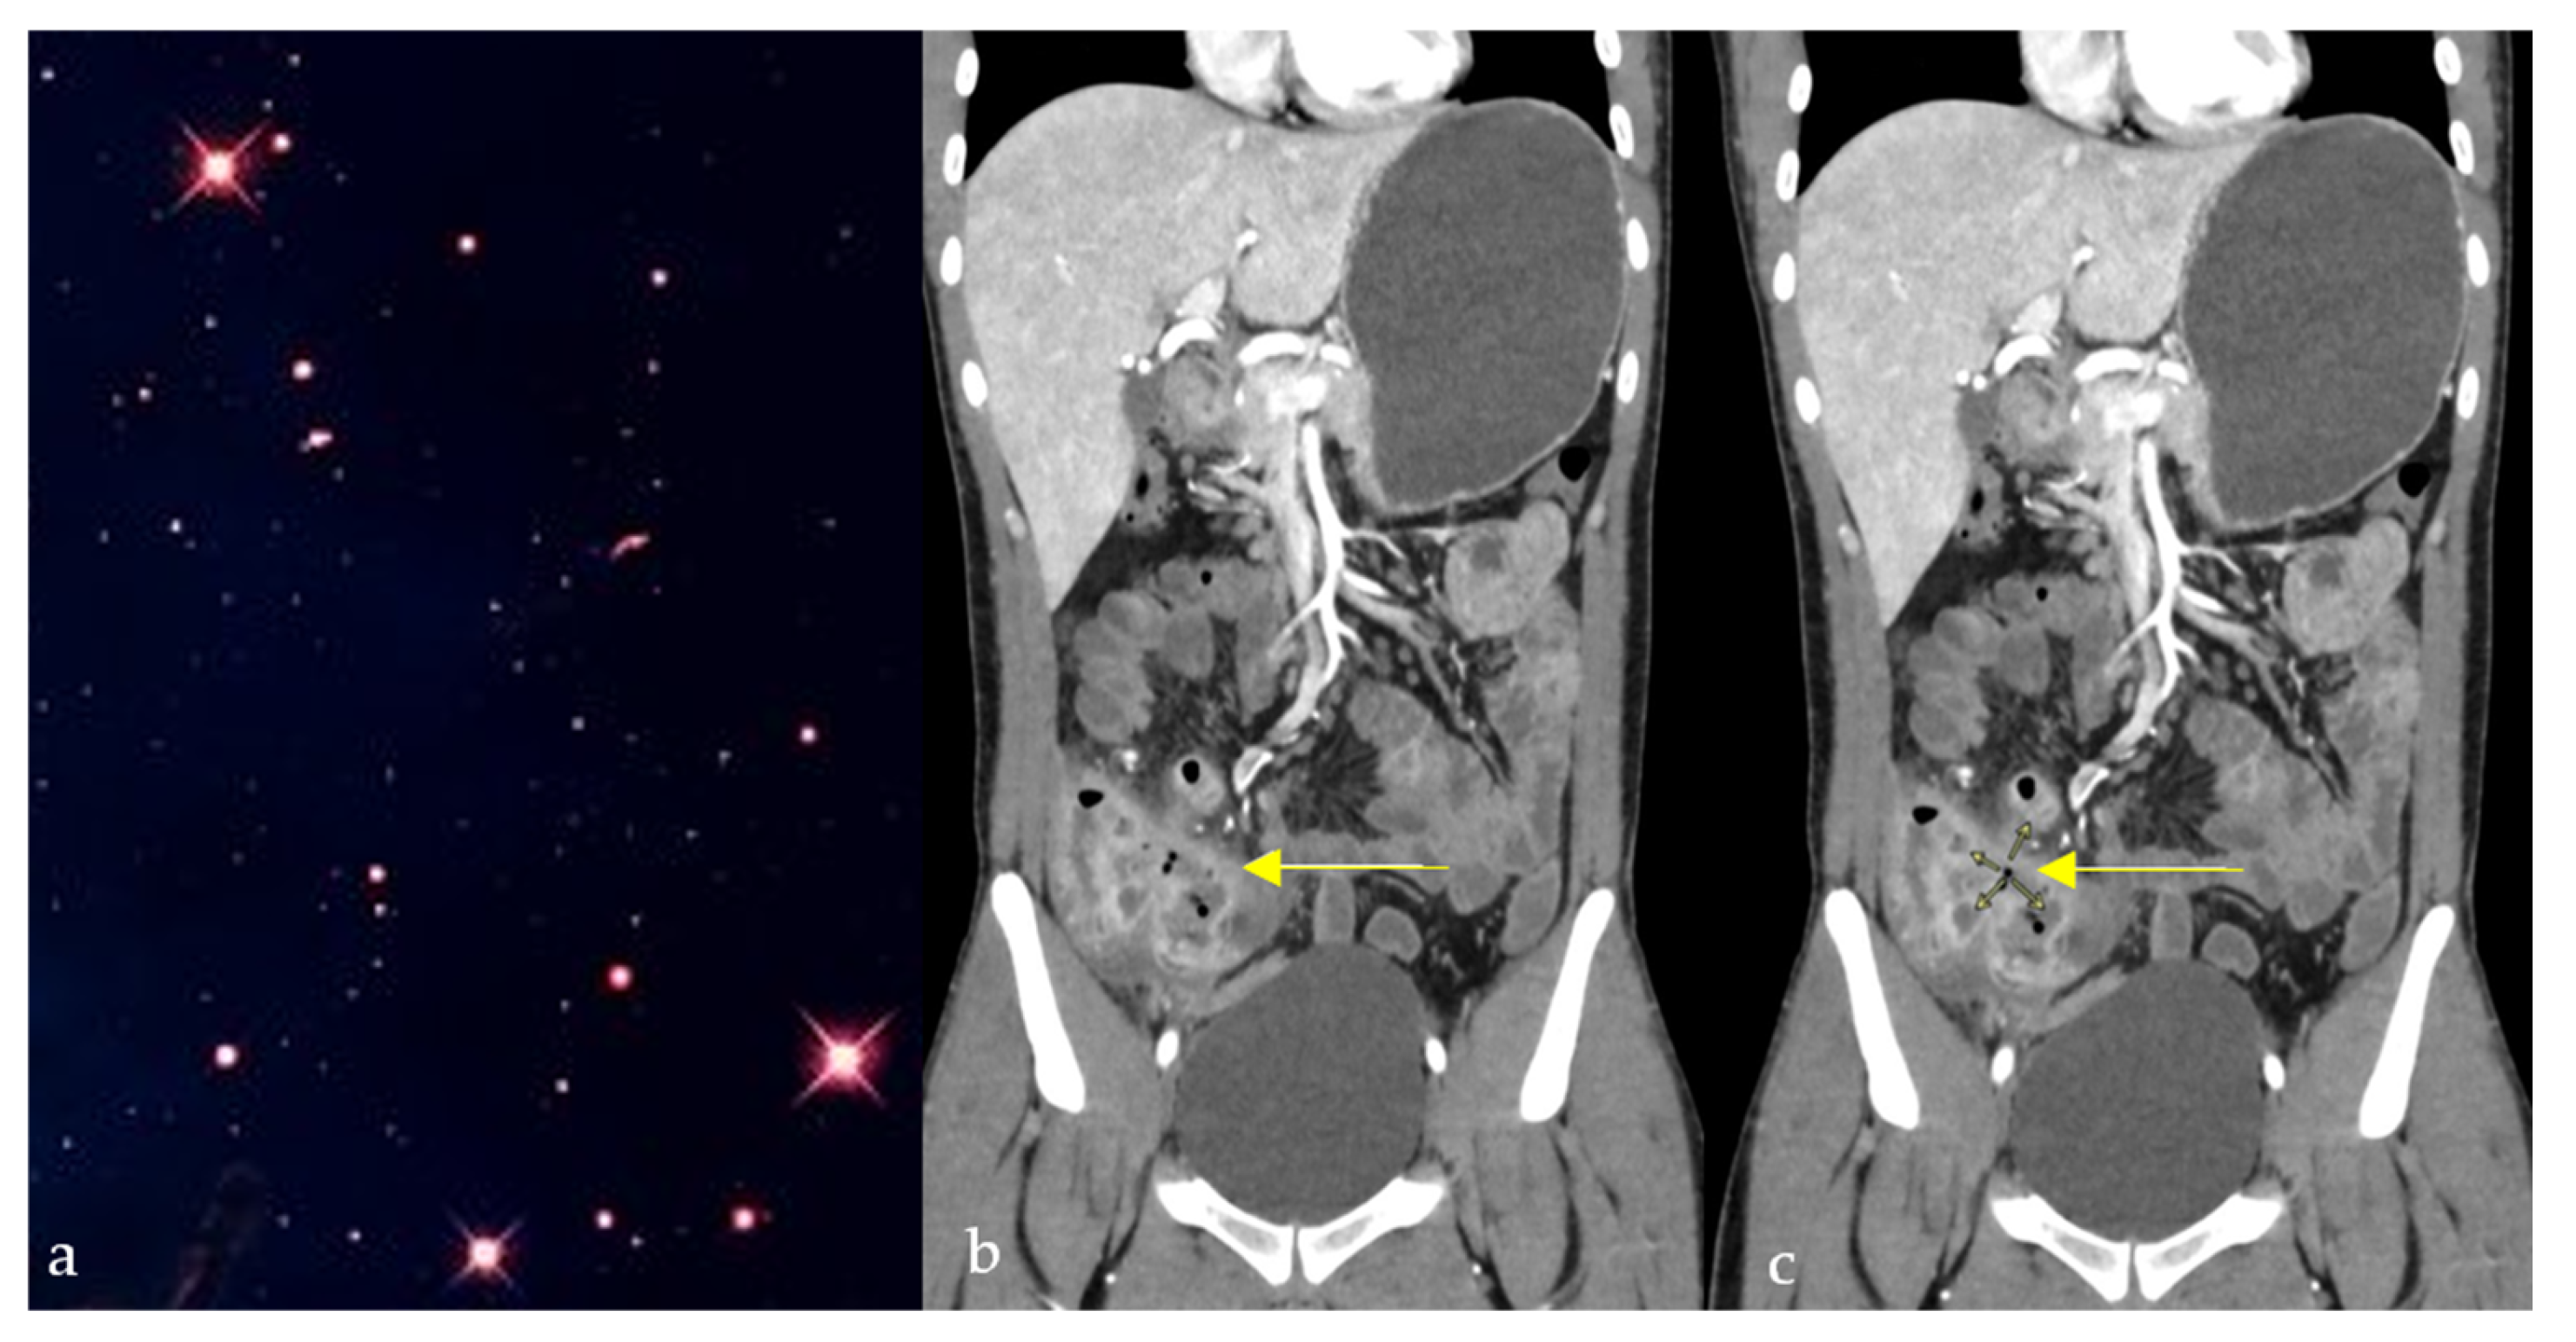

2.7. Star Sign

The star sign describes the pathognomonic appearance of complex entero-enteric fistulas seen in cases of penetrating Crohn’s disease resembling a shining star (Figure 7a), typically appearing as high T2 and contrast-enhanced T1 tubular structures on magnetic resonance enterography (MRE), or less frequently, on CT enterography [32]. It results from severe inflammation causing ulcerations and multiple fistulous tracts, causing tethering of inflamed and edematous bowel loops, giving a stellate appearance (Figure 7b,c) [33]. The star sign has an estimated sensitivity and specificity of 78.6% and 96.7%, respectively [34]. In Crohn’s patients with abdominal pain, diarrhea, or perianal drainage, a stellate cluster of enhancing fistulous tracts on MRE (“star sign”) indicates a complex fistulizing disease requiring advanced medical or surgical therapy.

Figure 7.

Coronal CT images of the abdomen and pelvis showing a conglomerate of inflamed bowel loops interconnected by multiple fistulous tracts (b,c), giving a star-shaped configuration (yellow arrows) resembling its natural counterpart (a).